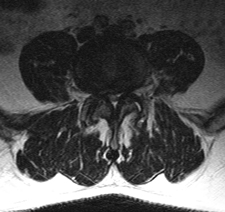

The narrowing of the spinal canal, called spinal stenosis, can happen as a result of the degeneration of both the facet joints and the intervertebral discs. In this condition, bone spurs, called osteophytes, which develop because of the excessive load on the intervertebral disc, grow into the spinal canal.

The facet joints also enlarge as they become arthritic, which contributes to a decrease in the space available for the nerve roots. The ligaments of the spinal column, especially the ligamentum flavum, become stiff, less flexible and thicker with age, which also contributes to spinal stenosis. These processes narrow the spinal canal and may begin to impinge and put pressure on the nerves roots and spinal cord, creating the symptoms of spinal stenosis.

Stenosis may occur in the central spinal canal (central stenosis) where the spinal cord or cauda equina are located, in the tract where the nerve root exits the central canal (lateral recess stenosis) or in the lateral foramen (foraminal stenosis) where the individual nerve roots exit out to the body.